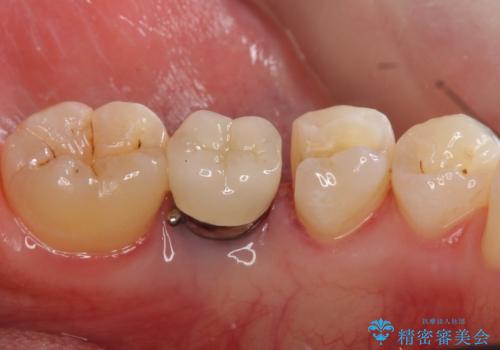

- 下の奥の銀歯を白くしたいとのことで来院されました。

セラミックインレーでの治療を行いました。

- 左下5 セラミックインレー 77,000円費用は治療当時の料金となります

銀の詰め物のやり替えは2回の来院で終わらせることができます。

下の歯は口を開けたときに外からよく見えるため、セラミックにやり替えることで印象が大きく変わります。